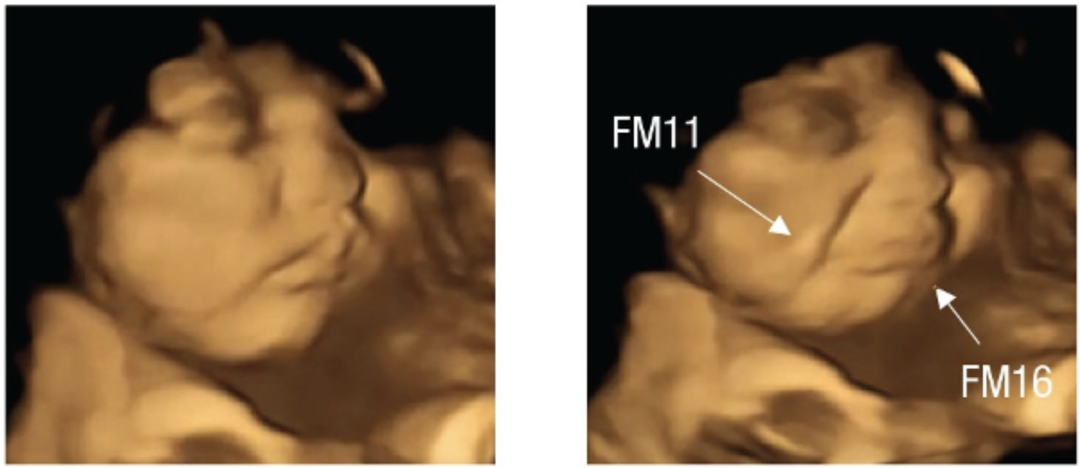

2022 年 9 月,一项发表在 Psychological Science 上的研究首次拍到了胎儿对母亲所吃食物的味道的面部反应。

研究人员把 100 名怀孕 32~36 周的孕妇分为两组,一组服用羽衣甘蓝粉,一组服用胡萝卜粉。然后 20 分钟后对孕妇腹部进行 4D 超声波扫描,惊奇地发现:

面对带「苦味的羽衣甘蓝」,胎儿更多给予的是一副哭脸;而对「带甜味的胡萝卜」,胎儿则更多地报以「笑脸」。

左为正常情况下胎儿的表情,右为羽衣甘蓝组宝宝的哭脸表情。

图片来源:参考文献 [16]

左为正常情况下胎儿的表情,右为胡萝卜组宝宝的笑脸表情。

图片来源:参考文献 [16]